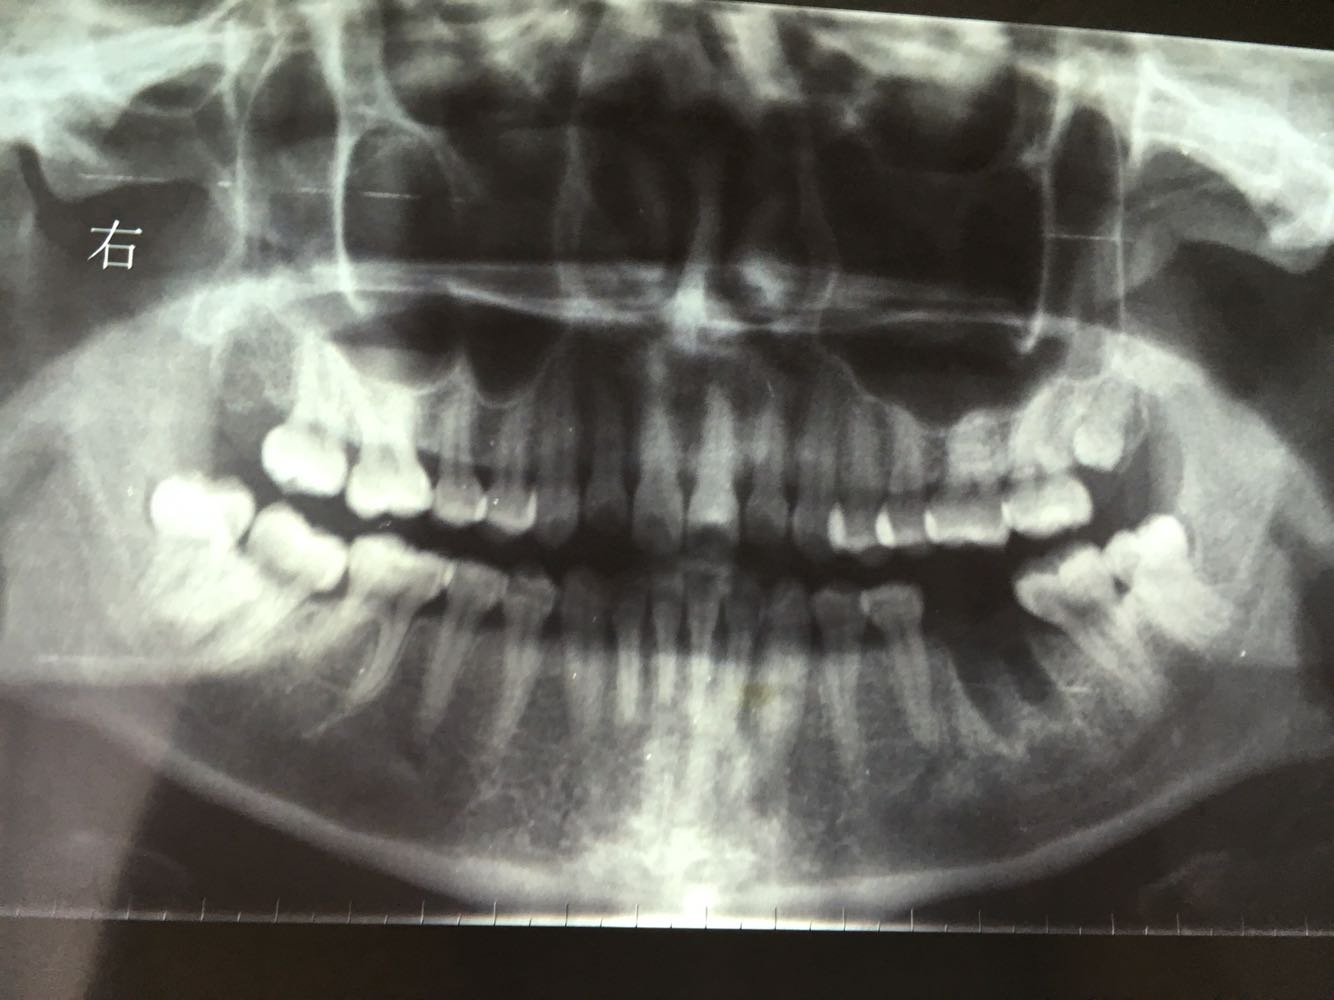

主诉:左下后牙反复肿痛

左下6残根,8正位,对颌未萌出,

讨论:患者本来是要求拔除左下6残根的,进修医生拔除残根后本人建议自体牙移植,患者接受了我的经验,把8拔除后移植到6的位置,目前还在随访中